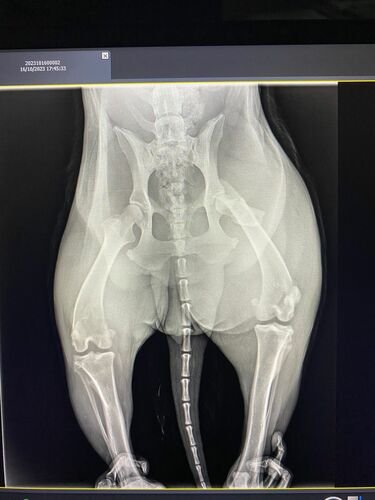

Sou Laís Dotta, e em setembro fiz vários anúncios com o meu irmão em busca da nossa cachorra Pandora uma rottweiler linda e mto amada que fugiu no sítio dia 15/09/2023, infelizmente até hj ainda não a encontramos, mas no meio do caminho dessa busca nos apareceu a Athena (nome dado a cachorra pela minha mãe) uma cachorra aparentemente mto sofrida, e não conseguimos deixar-la para trás sem a resgatar para ajuda lá, pois ela estava machucada, meu irmão a levou no hospital público, aí veio a notícia que a perna estava fraturada e ela ia ter que fazer uma cirurgia, mas infelizmente essa cirurgia era 4 mil reais e eles não conseguiram a cirurgia para ela, a devolveram pro meu irmão, assim desde então ela está sendo cuidada na casa da minha mãe a base de medicamentos e amor, mas Deus guiou minha mãe ao lugar certo, e conseguimos uma “caridade” para operar a Athena por $1600,00 , onde ainda infelizmente não temos esse dinheiro, pois já gastamos mto com ela e depois da cirurgia ainda vão ter mtos outros medicamentos…… então hj com ideia de amigos estamos aqui para pedir a vcs uma ajuda para salvar essa guerreira linda…..